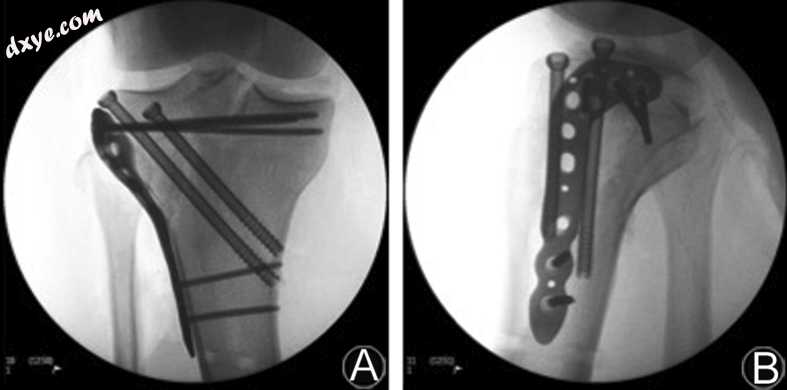

在潜伏期为12天(软组织复苏的足够时间)后,患者前往手术室进行右胫骨平台骨折的明确固定。进行了胫骨近端的前外侧入路。确定,准备,清洁和减少裂缝。用两根3.2毫米的k线暂时减少了压下量。从近端到远端和前外侧到内侧施加两个插管的6.5mm部分螺纹螺钉(ASNIS III 6.5mm,Stryker,Kalamazoo,MI,USA),以提供穿过骨折剪切平面的压缩。在支撑模式(AxSOS 3,Stryker,Kalamazoo,MI,USA)中应用另外的外侧胫骨近端板(图3A和B)。手术过程中没有并发症。

图3

图像识别器射线照片的前后(A)和侧(B)术中视图描绘右胫骨近端外科固定。